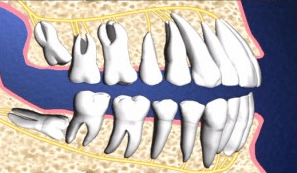

- Răng khôn là răng hàm cuối cùng của mỗi bên hàm. Răng khôn cũng là răng được mọc cuối cùng, thường là khi người ta ở độ tuổi 16 đến 20.

- Vì răng khôn là những chiếc răng vĩnh viễn mọc lên sau cùng, nên thường vòm miệng của bạn không có đủ chỗ dành cho chúng . Điều này có thể ảnh hưởng đến các răng khôn như răng có thể bị kẹt lại dưới mô nướu bởi các răng khác hoặc xương hàm. Nếu răng khôn bị tác động, có thể dẫn đến sưng và đau.

- Răng khôn mọc ngầm tạo nang trong xương hàm

- Răng khôn hàm trên và dưới thường bị mọc lệch

- Răng khôn mọc lệch làm hư răng 7, sau khi mất răng 7 răng đối diện bị trồi